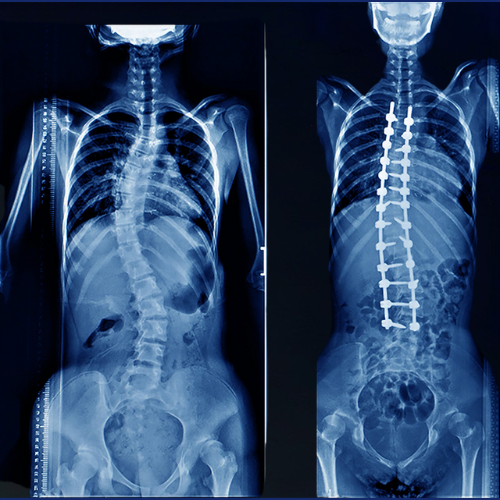

Scoliosis is an abnormal sideways curvature of the spine that can occur in children, adolescents, or even adults. Without timely treatment, scoliosis may leadRead More